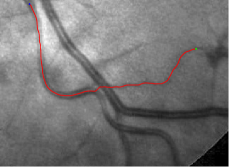

Compare to existing minimal path models. The Riemannian metrics used in [1, 4, 5] are based on the local pointwise information. The curvature-penalized metric [7, 6] and the proposed coherence-penalized metric are able to consider more constraints, i.e., the rigidity for [7, 6] and feature coherence for our metric. These constraints are beneficial to the respective geodesics to reduce the risk of short branches combination problem. Compared to the curvature-penalized metric, our method can be more flexible since the feature map can be produced dependently on the task. In retinal imaging, veins and arteries are distinguishable in terms of gray levels or vesselness values, satisfying the formulation of the proposed model. Especially for vessels with strong tortuosity, the curvature-penalized metric, which favours a smooth curve, fails to catch the expected vessels as shown in the left column of Fig. 2. From the right column of Fig. 2, one can see that our model can obtain a good result.

Validation. We validate our minimal path model on respective 54 and 30 patches obtained from the DRIVE [14, 15] and the IOSTAR [16] datasets with AV groundtruth. Each artery involved in these parches locates near a vein or crossing it at least once. Our goal is to extract the artery between two given points. In order to get the quantitative evaluation, we first convert each continuous spatial path to an 4-connected digital path which is considered as a pixel collection. We denote by the collection of digital path pixels inside the artery groundtruth map . Thus, a measure can be simply defined as , where and mean the respective number of elements involved in and . We compare our model to four existing minimal path models: the isotropic Riemannian (IR) model [1], the anisotropic radius-lifted Riemannian (ArR) model [4], the isotropic orientation-lifted Riemannian (IoR) model [5] and the curvature-penalized (CuP) model [7]. The construction of these metrics are based on the OOF outputs [12]. Note that a centerline-based potential is chosen so that we remove the radius dimension of [5] to reduce computation complexity. The results in terms of the score are presented in Table 1, including the average (Avg.), maximum (Max.), minimum (Min.) and standard deviation (Std.) values. In both DRIVE and IOSTAR datasets, our method can achieve the best performances thanks to the coherence penalization. Note that in Table 1, we evaluate our method by using the refined paths instead of using the original coherence-penalized minimal paths. For comparisons in visualization, we show the minimal paths from the ArR metric , the CuP metric and the proposed coherence-penalized metric on three retinal patches as shown in Fig. 3. The targeted artery vessels which cross veins at least once are labeled by red color in column 1. The paths shown in column 4 from the proposed metric are results after refinement. One can claim that our method indeed can catch expected arteries while other metrics fall into the traps of short branches combination.